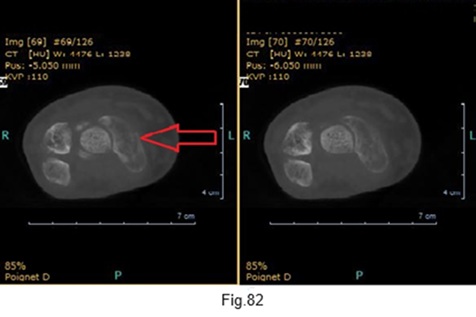

Le scanner montre que la fracture est consolidée (Fig.82).